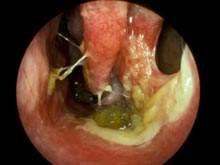

症状一:鼻粘膜溃疡、糜烂常见于鼻中隔前下区(Little区),多由慢性炎症引起。化学性气体、高温、干燥空气皆可成为诱因。此外,鼻中隔棘突或矩状突、鼻中隔穿孔、萎缩性鼻炎,也可引起局部鼻粘膜溃疡形成而导致出血。鼻窦的急性感染。

相关图片